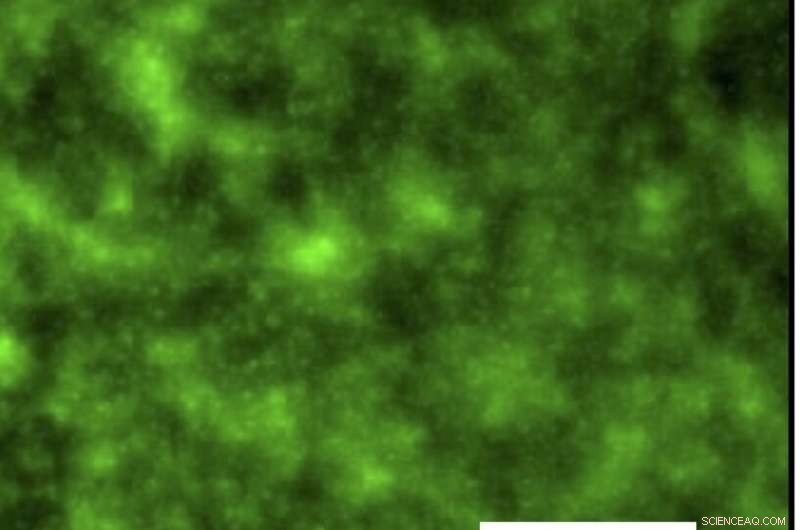

After 24 hours, a bacterial pathogen, Pseudomonas aeruginosa (green), has attached to a bare glass slide, but not to a SLIPS-coated slide that contains an antibacterial agent. Credit: David Lynn, Materials Views, 2016

With Helen Blackwell, a professor of chemistry at UW–Madison with extensive understanding of bacterial growth, Lynn has demonstrated that the "slippery liquid-infused porous surfaces" (SLIPS) indeed prevent bacteria from growing on glass surfaces.